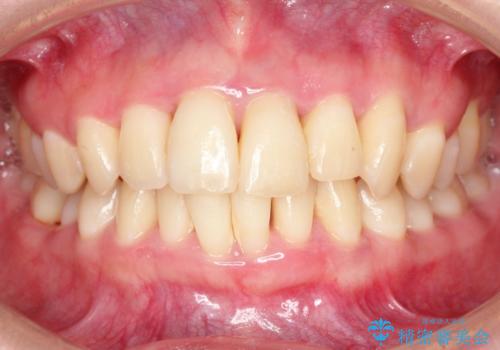

侵襲性歯周炎。前歯の歯周補綴

治療症例の内容

- 前歯がグラグラすることを主訴に来院されました。

再生治療後、歯周補綴を行っております。

歯周病が進行してしまった歯に対し、再生治療および歯周補綴を行うことで歯周組織の安定を得ることができました。